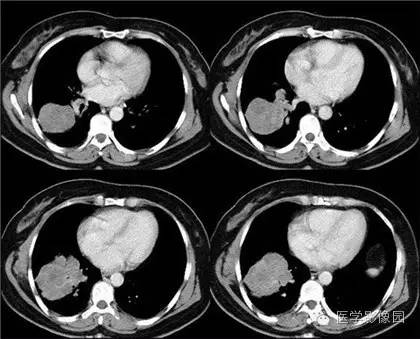

4、新藥:NSCLC術(shù)后輔助治療!奧希替尼在華新適應(yīng)證上市申請(qǐng)擬納入優(yōu)先審評(píng)

10月12日,阿斯利康在中國(guó)提交的甲磺酸奧希替尼片上市申請(qǐng)擬納入優(yōu)先審評(píng),用于具有表皮生長(zhǎng)因子受體(EGFR)敏感突變的非小細(xì)胞肺癌(NSCLC)成人患者腫瘤切除術(shù)后的輔助治療。

2020歐洲腫瘤內(nèi)科學(xué)會(huì)(ESMO)大會(huì)上公布的III期ADAURA研究數(shù)據(jù)顯示,奧希替尼在對(duì)接受過(guò)完全腫瘤切除術(shù)的早期(IB、II和IIIA期)EGFRm NSCLC患者的輔助治療中,可帶來(lái)具有臨床意義的中樞神經(jīng)系統(tǒng)(CNS)無(wú)病生存期(DFS)改善。奧希替尼輔助治療組較安慰劑組有更少患者出現(xiàn)了復(fù)發(fā)或死亡 (11% vs. 46%)。

在已出現(xiàn)疾病復(fù)發(fā)的患者中,奧希替尼組中有38%的患者出現(xiàn)了轉(zhuǎn)移性復(fù)發(fā),而安慰劑組為61%。奧希替尼可顯著降低中樞神經(jīng)系統(tǒng)復(fù)發(fā)或死亡風(fēng)險(xiǎn)82%(HR 0.18)。兩組均未達(dá)到中位中樞神經(jīng)系統(tǒng)無(wú)病生存期 (CNS DFS)。

此外,好醫(yī)友了解到,一項(xiàng)事后分析提示,在既往未出現(xiàn)其他部位復(fù)發(fā)的患者中,接受奧希替尼治療的患者18個(gè)月時(shí)出現(xiàn)腦部疾病復(fù)發(fā)的估算幾率低于1%,而安慰劑組為9%。主要研究終點(diǎn)II期和IIIA期患者的DFS,奧希替尼輔助治療降低了83%疾病復(fù)發(fā)或死亡的風(fēng)險(xiǎn)(HR 0.17)。